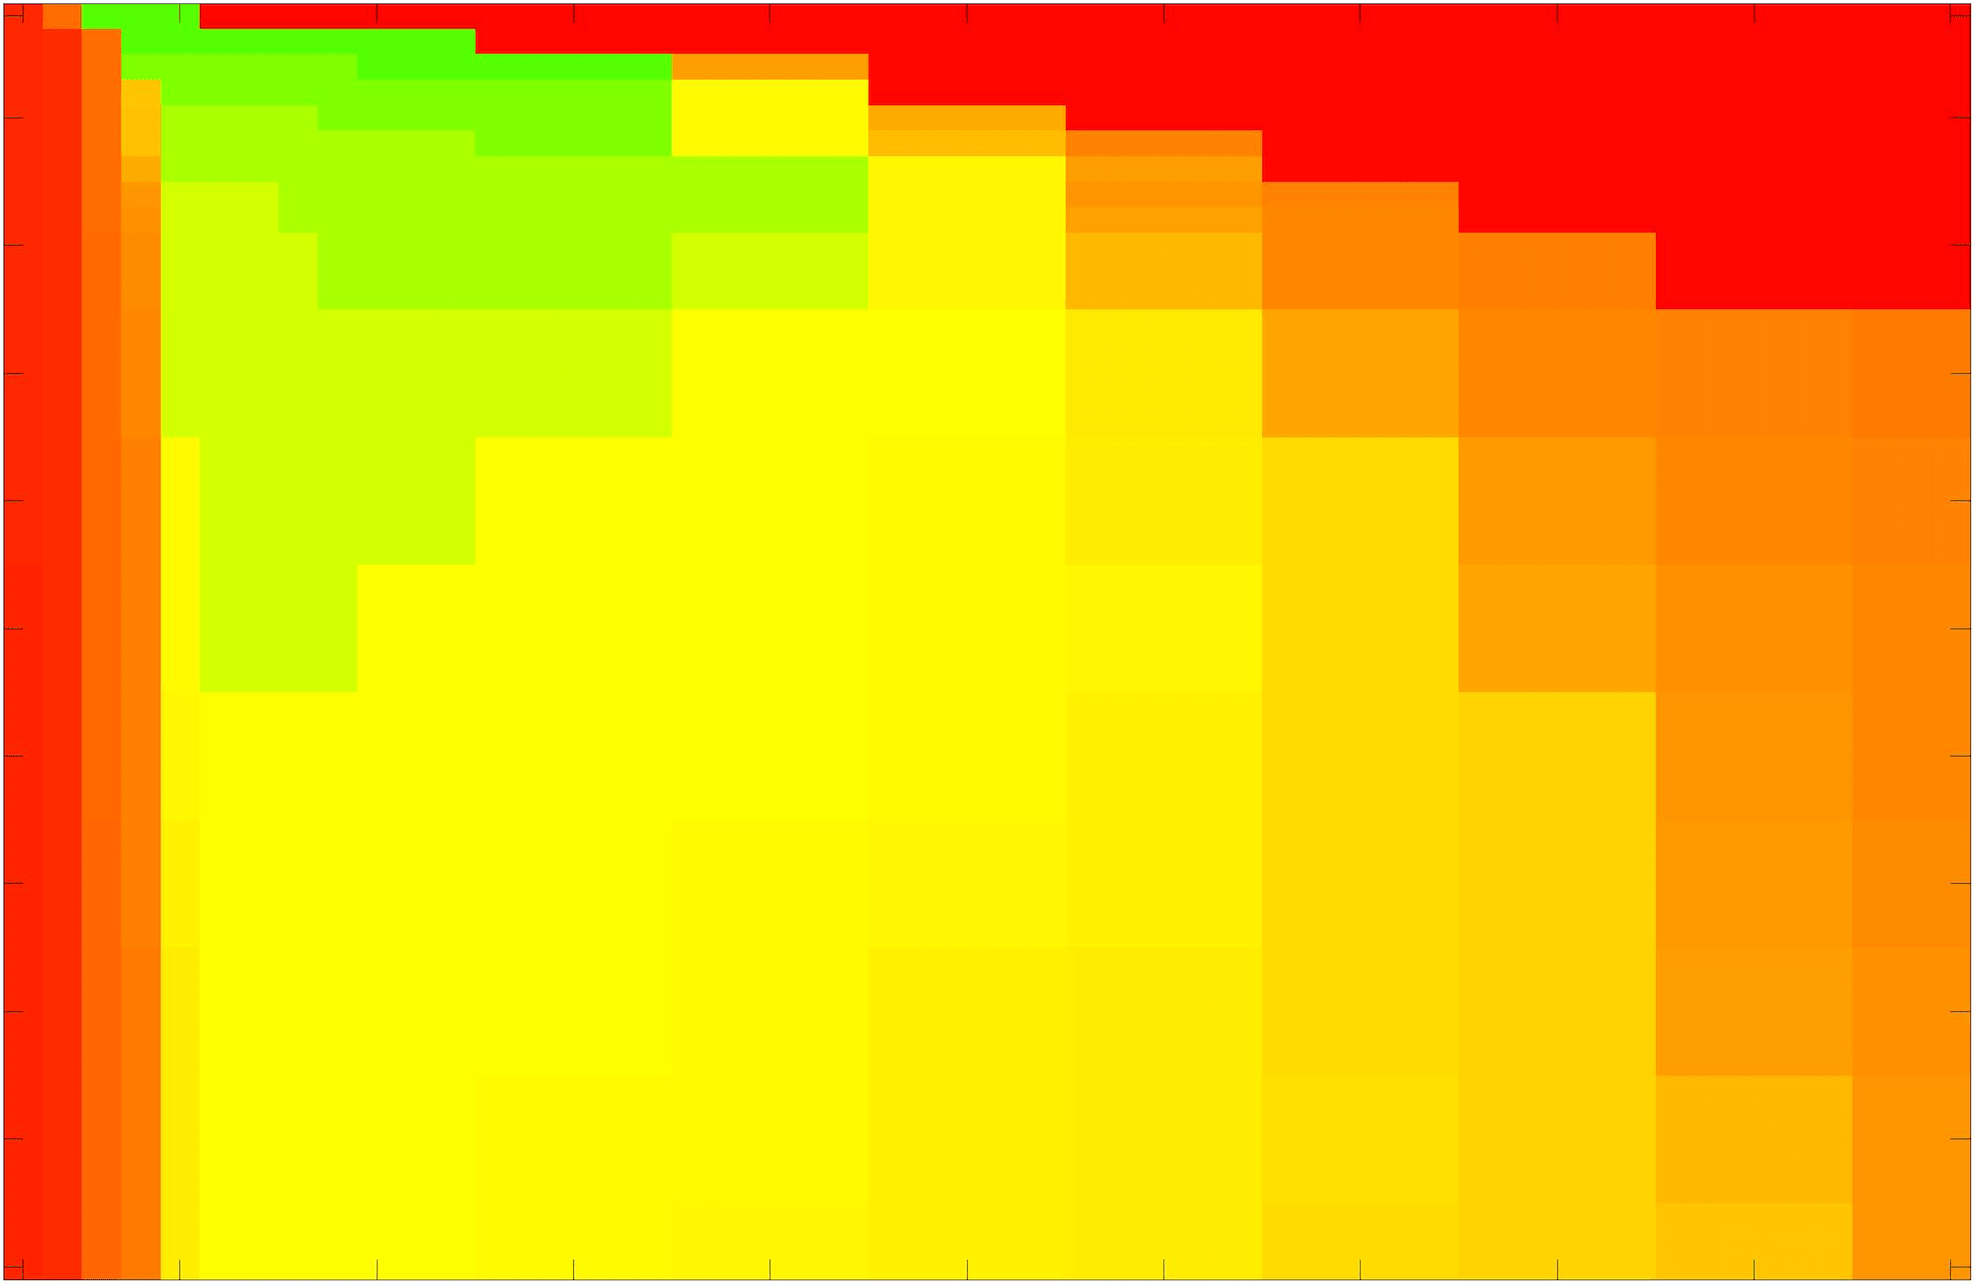

In these tests we aim to demonstrate how sensitive to parameter choices each choice of fitting term is. To accomplish this we perform the segmentations for each of the models discussed (CV, RSF, LCV, HYB, GAV) and the proposed model for a wide range of parameters and compute the TC value. The parameter range used is . Due to computational constraints, we run for each integer between 1 and 10, and every fifth from 15 to 50. This aspect of a model’s performance is vital when used in practice. The less sensitive to parameter choices a model is the more relevant it is in relation to potential applications. It should be noted that we neglect to test the selective models detailed in §3 with respect to parameter robustness as we are using the authors’ implementation of each approach. Instead, we make direct comparisons in the following sections.

The TC values for the parameter sets are presented as heatmaps in Figs. 11–13. A heatmap is a convenient way to display accuracy results for hundreds of tests concisely. In Fig. 9 we give an example heatmap with the same axes used for those in Figs. 11–13. For each of the combinations of parameter values we give the TC value of the segmentation result and represent it by the appropriate colour. The corresponding colour scale is shown in Fig. 8. Qualitatively, the more green areas of the heatmap the more accurate the model is for a wider set of parameters. Example results for Test Image 5 when varying (with ) for the proposed model are given in Fig. 10. Here it can be seen what each accuracy result corresponds to visually.

Synthetic Images. These results are presented in Fig. 11. For Test Images 1–2 we see poor parameter robustness from all competing models, except for GAV which performs reasonably well. However, the proposed model has minimal parameter sensitivity for these images, with good results achieved for almost every combination of values tested. For Test Image 3 all models have a reasonable parameter range (except for RSF), however the proposed model gives better quality results for a wider parameter range. The other models achieve reasonable results here as the foreground intensity of the ground truth is greater than the background , whereas for Test Images 1–2 they are equal . These results highlight the key advantage of the proposed model.

Real Images. In Fig 12 we present results for Test Images 4–6. Here, the proposed model performs in a similar way to its competitors because these images are more typical selective segmentation problems in the sense that there is a clear distinction between the foreground and background intensities. In particular, the values in each case are: Test Image 4 , Test Image 5 , and Test Image 6 . It can be seen that the proposed model is competitive compared to previous approaches. The performance is quite poor for Test Image 5, but is arguably still the best for this challenging case. In Fig. 13 we present results for Test Images 7–9. Here the proposed model outperforms previous approaches significantly for each image. This is mainly due to the type of image considered. Specifically, the true intensities are: Test Image 7 , Test Image 8 , and Test Image 9 . The proposed model is capable of achieving results where , with other models failing completely in these cases.